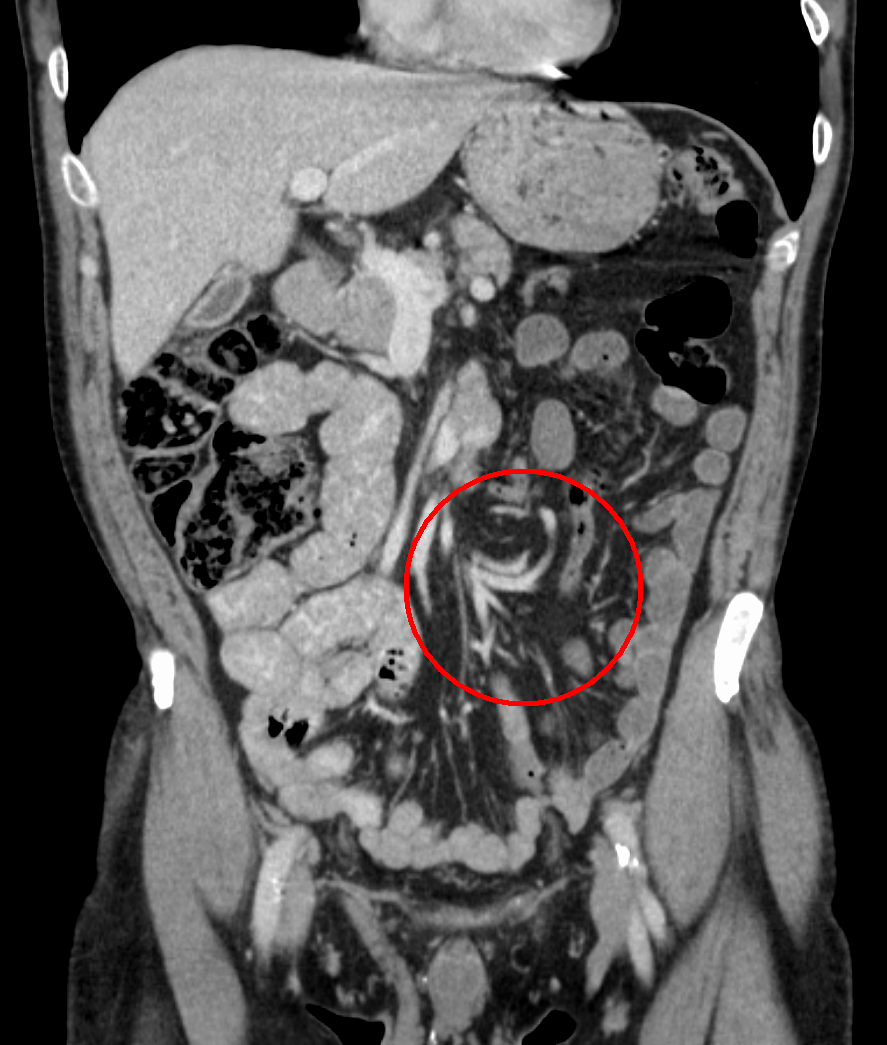

From www.researchgate.net

(PDF) Acute abdomen due to Jpouch outlet obstruction A case report J Pouch Blockage Learn about the candidates, risks, benefits, and recovery of this alternative to ileostomy. This procedure completely removes the diseased colon while retaining transanal defecation. It involves removing the colon. J Pouch Blockage.